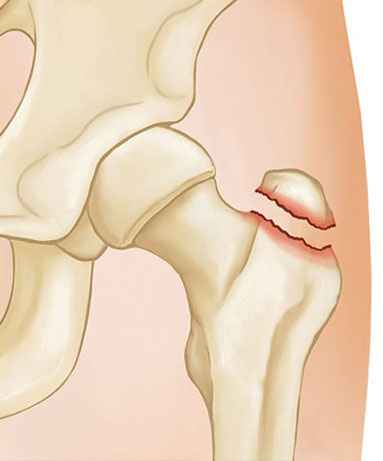

Fracture of the Greater Trochanter

Isolated fractures of the greater trochanter usually come from a low-energy household fall. While they are often painful, they usually heal without surgery. These fractures are stable and can be treated with protected weightbearing using either crutches or a walker.

An isolated fracture of the greater trochanter

If an X-ray shows an isolated fracture of the greater trochanter, it is often helpful to get a CT scan to make sure that the fracture does not extend to the intertrochanteric area.